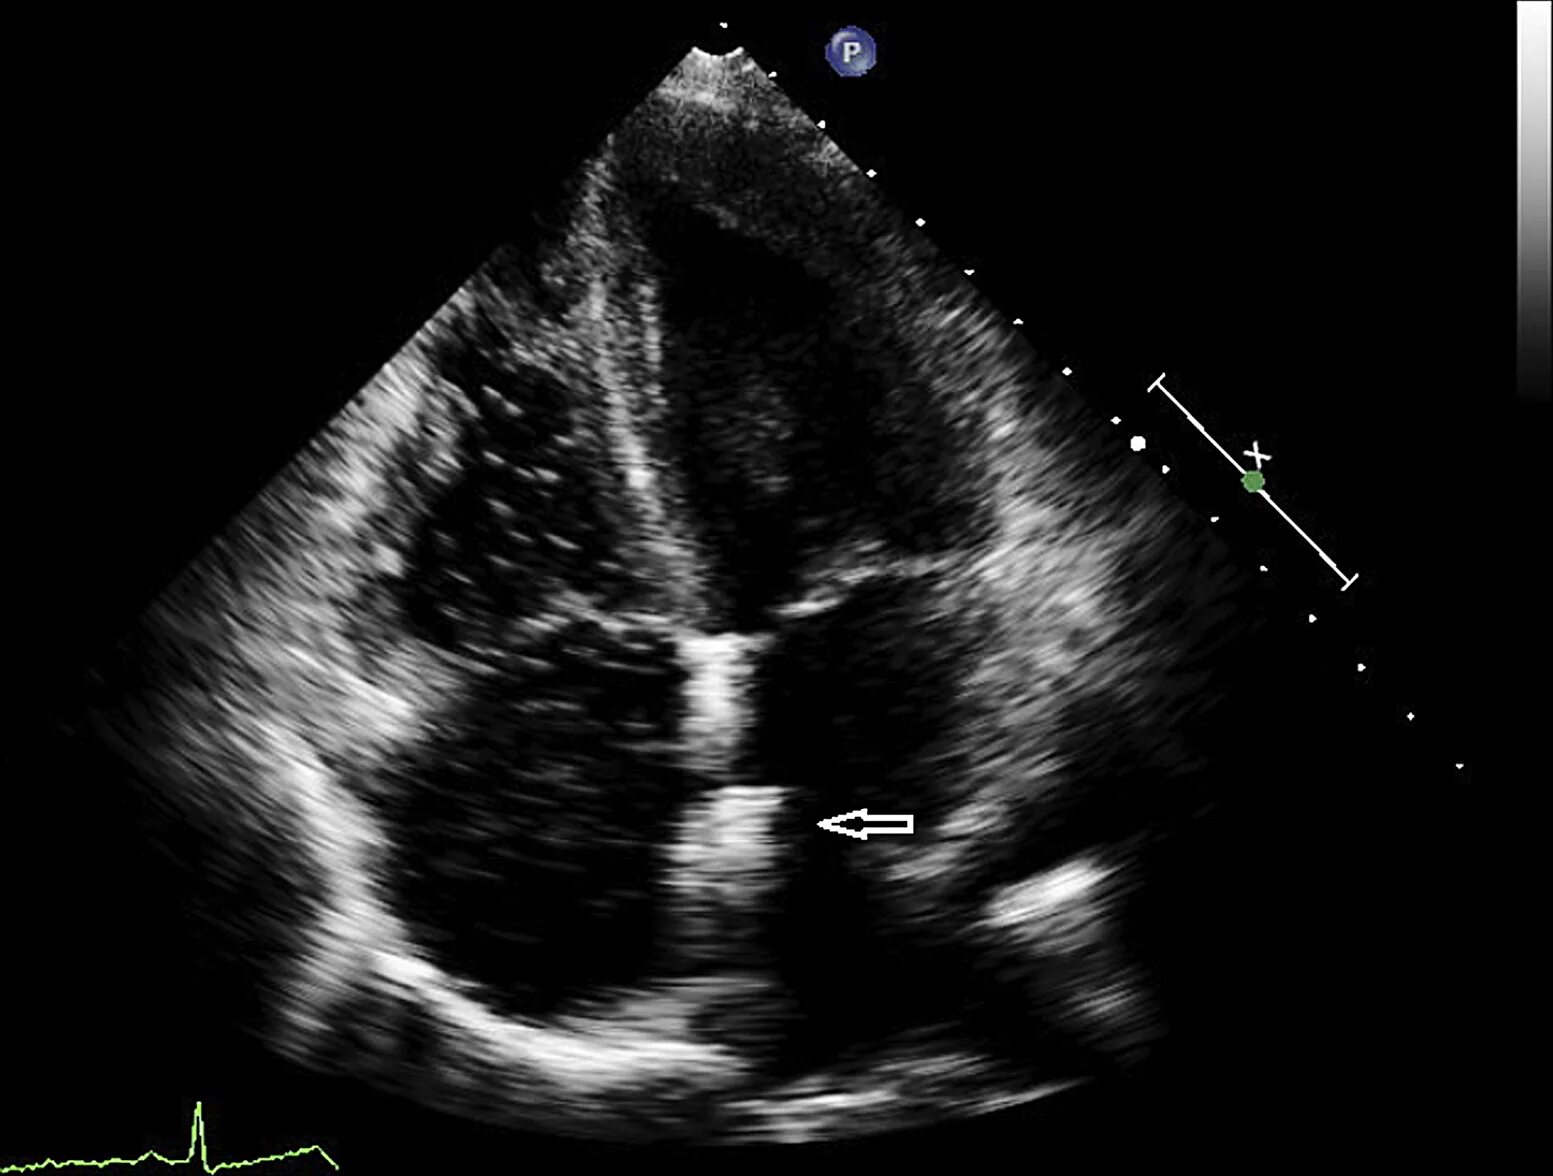

Окно в сердце у новорожденного